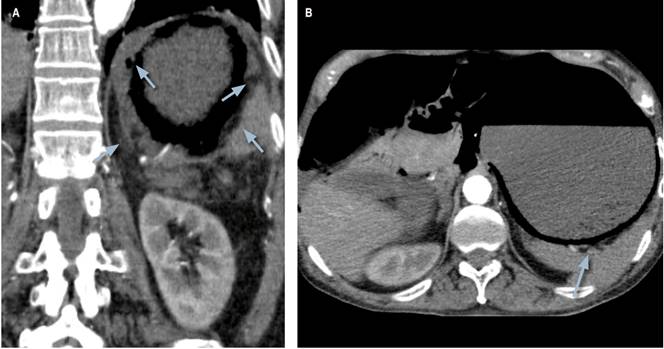

Se trataba de un paciente de 76 años, masculino, con antecedentes de enfermedad de Alzheimer avanzada e hipertensión arterial. Ingresó por un cuadro clínico de 12 horas de evolución consistente en dolor abdominal intenso que inició en la región epigástrica, con irradiación a mesogastrio, tipo cólico y asociado con picos febriles no cuantificados. Negaba emesis, cambios en las deposiciones u otra sintomatología asociada. A la revisión por sistemas, su hija manifestaba pérdida no voluntaria de peso (7 kilos en 3 meses, aproximadamente). Al ingreso se apreciaba un paciente taquicárdico y febril, con tendencia a la hipotensión, con marcada distensión abdominal y dolor a la palpación generalizada, palidez generalizada, frialdad distal y signos leves de dificultad respiratoria. Se indicó la toma de analítica de ingreso y se encontró una marcada leucocitosis y neutrofilia, función renal alterada y gases arteriales que evidenciaban acidosis metabólica grave con trastorno moderado de la oxigenación e hiperlactatemia (Tabla 1). Se establece un puntaje SOFA de ingreso de 6 puntos. Se indicó la toma de una tomografía de urgencia que evidenciaba la sobredistensión de cámara gástrica con neumatosis intestinal, portograma aéreo y engrosamiento de la pared gástrica con burbujas de gas en su interior (Figura 1).

Algunos autores han descrito la diferenciación imagenológica entre enfisema gástrico y gastritis enfisematosa. Se ha descrito que el hallazgo tomográfico más importante en el enfisema gástrico consiste en bandas lineales de aire que siguen la disposición de las capas de la pared gástrica. En el enfisema gástrico no suele existir engrosamiento de la mucosa 10. No existe un estándar de oro para el diagnóstico de la gastritis enfisematosa. Se ha propuesto que la sospecha clínica en combinación con la radiografía simple de abdomen es suficiente para orientar un diagnóstico 8. Sin embargo, el amplio desconocimiento de la enfermedad podría dar lugar a que esta combinación no sea suficiente para soportar un diagnóstico cercano. La tomografía de abdomen posee mayor sensibilidad y especificidad para la detección de gas intramural 2. Los hallazgos imagenológicos que se aprecian en las tomografías de pacientes con gastritis enfisematosa incluyen quistes de aire que infiltran la pared de la cámara gástrica, neumoperitoneo y gas en el sistema portal 4,8. También se describe engrosamiento de la pared de la cámara gástrica con edema de la submucosa y abscesos intramurales 8,11. Es más común el hallazgo de neumatosis intestinal y neumoperitoneo en la gastritis enfisematosa que en el enfisema gástrico 10.